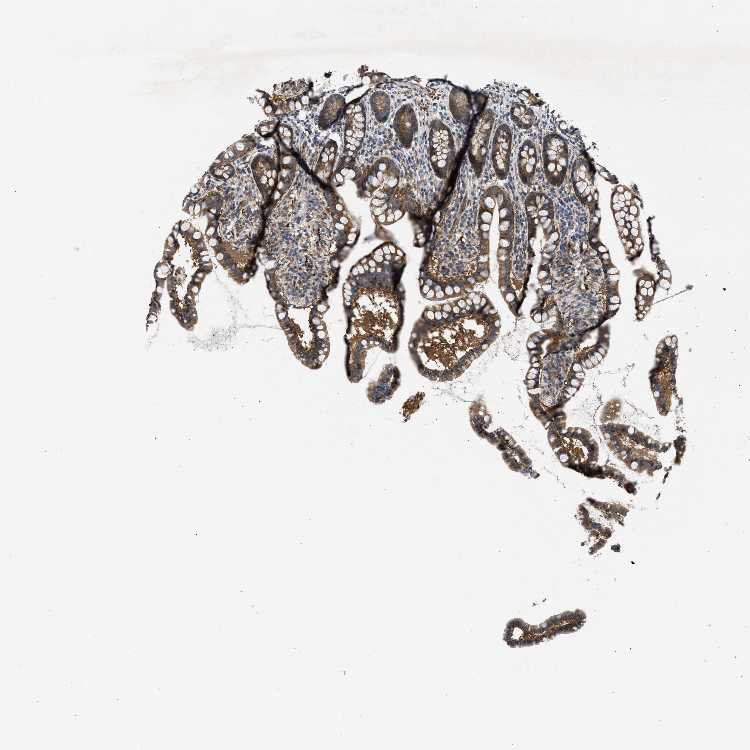

ZNF599